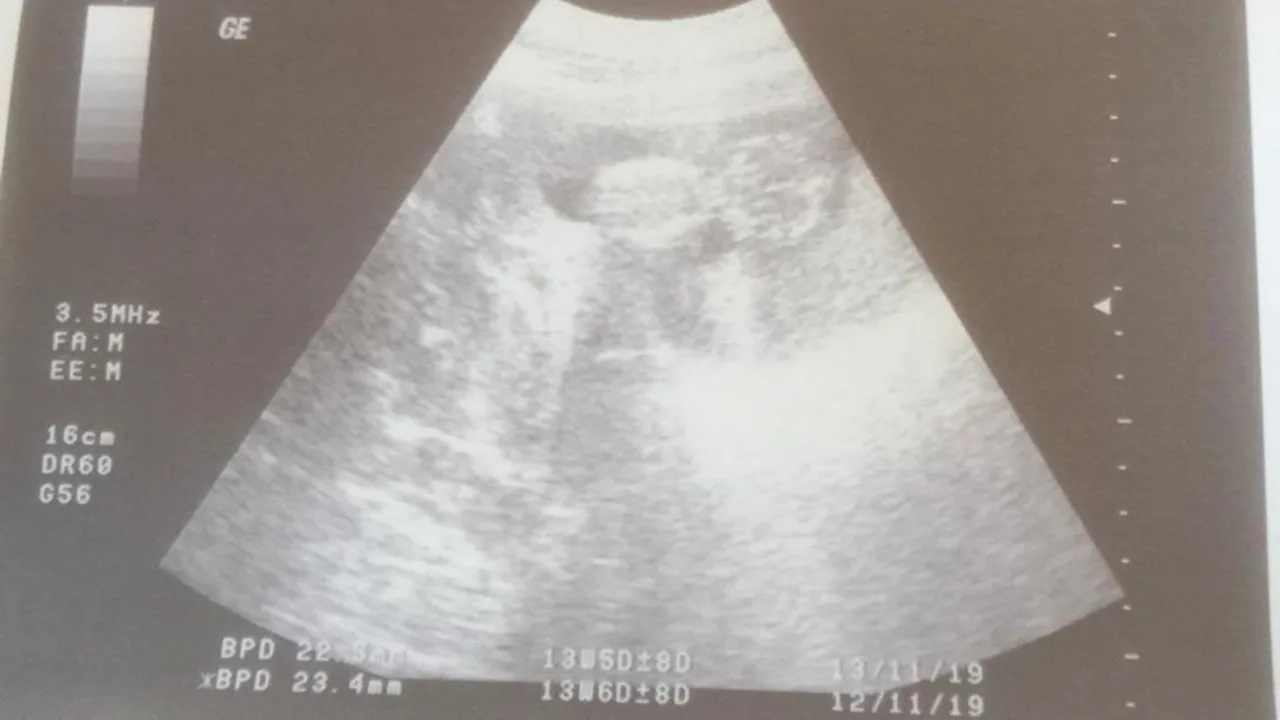

Bebeğin anne karnındaki gelişimi, rutin ultrason muayeneleri ile yakından takip edilir. Ultrason sırasında bebeğin baş çevresi (BPD), karın çevresi (AC) ve uyluk kemiği uzunluğu (FL) gibi ölçümler alınır. Bu ölçümler, özel formüller kullanılarak bebeğin tahmini ağırlığını (EFW - Estimated Fetal Weight) belirlemek için kullanılır.

Unutulmaması gereken: Ultrasonla yapılan kilo tahminleri, ortalama %10-15 civarında bir yanılma payına sahip olabilir. Bu, bebeğin pozisyonu, amniyon sıvısı miktarı veya kullanılan cihazın hassasiyeti gibi faktörlere bağlı olarak gerçek kilodan biraz farklılık gösterebileceği anlamına gelir. Önemli olan, doktorunuzun bebeğinizin genel gelişimini, tüm ölçümlerini ve büyüme eğrisini bir bütün olarak değerlendirmesidir.